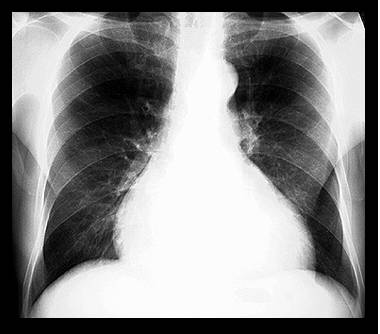

Radiografia pulmonara evidentiaza cardiomegalia ( creste indicele cardiotoracic) si semne de redistributie a circulatiei pulmonare - edemul interstitial si alveolar, hidrotoraxul.

- Electrocardiograma este aproape totdeauna modificata, fara specificitate. Evidentiaza frecvent tahicardia sinusala. Modificarile ST-T, invariabil prezente, sunt nespecifice. Se pot intalni semne de HVS, BRS, unde Q patologice si diverse aritmii.